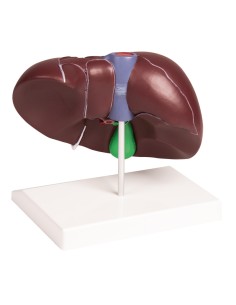

Dal cranio in 22 parti con incastri magnetici ai modelli di colonna vertebrale, da quelli di articolazioni a quelli di cuore, ogni pezzo della nostra collezione è progettato per un’immersione totale nello studio dell’anatomia umana. I nostri modelli, realizzati tramite scansioni di ossa vere, garantiscono un’esperienza tattile autentica e una fedeltà di peso quasi identica agli originali.